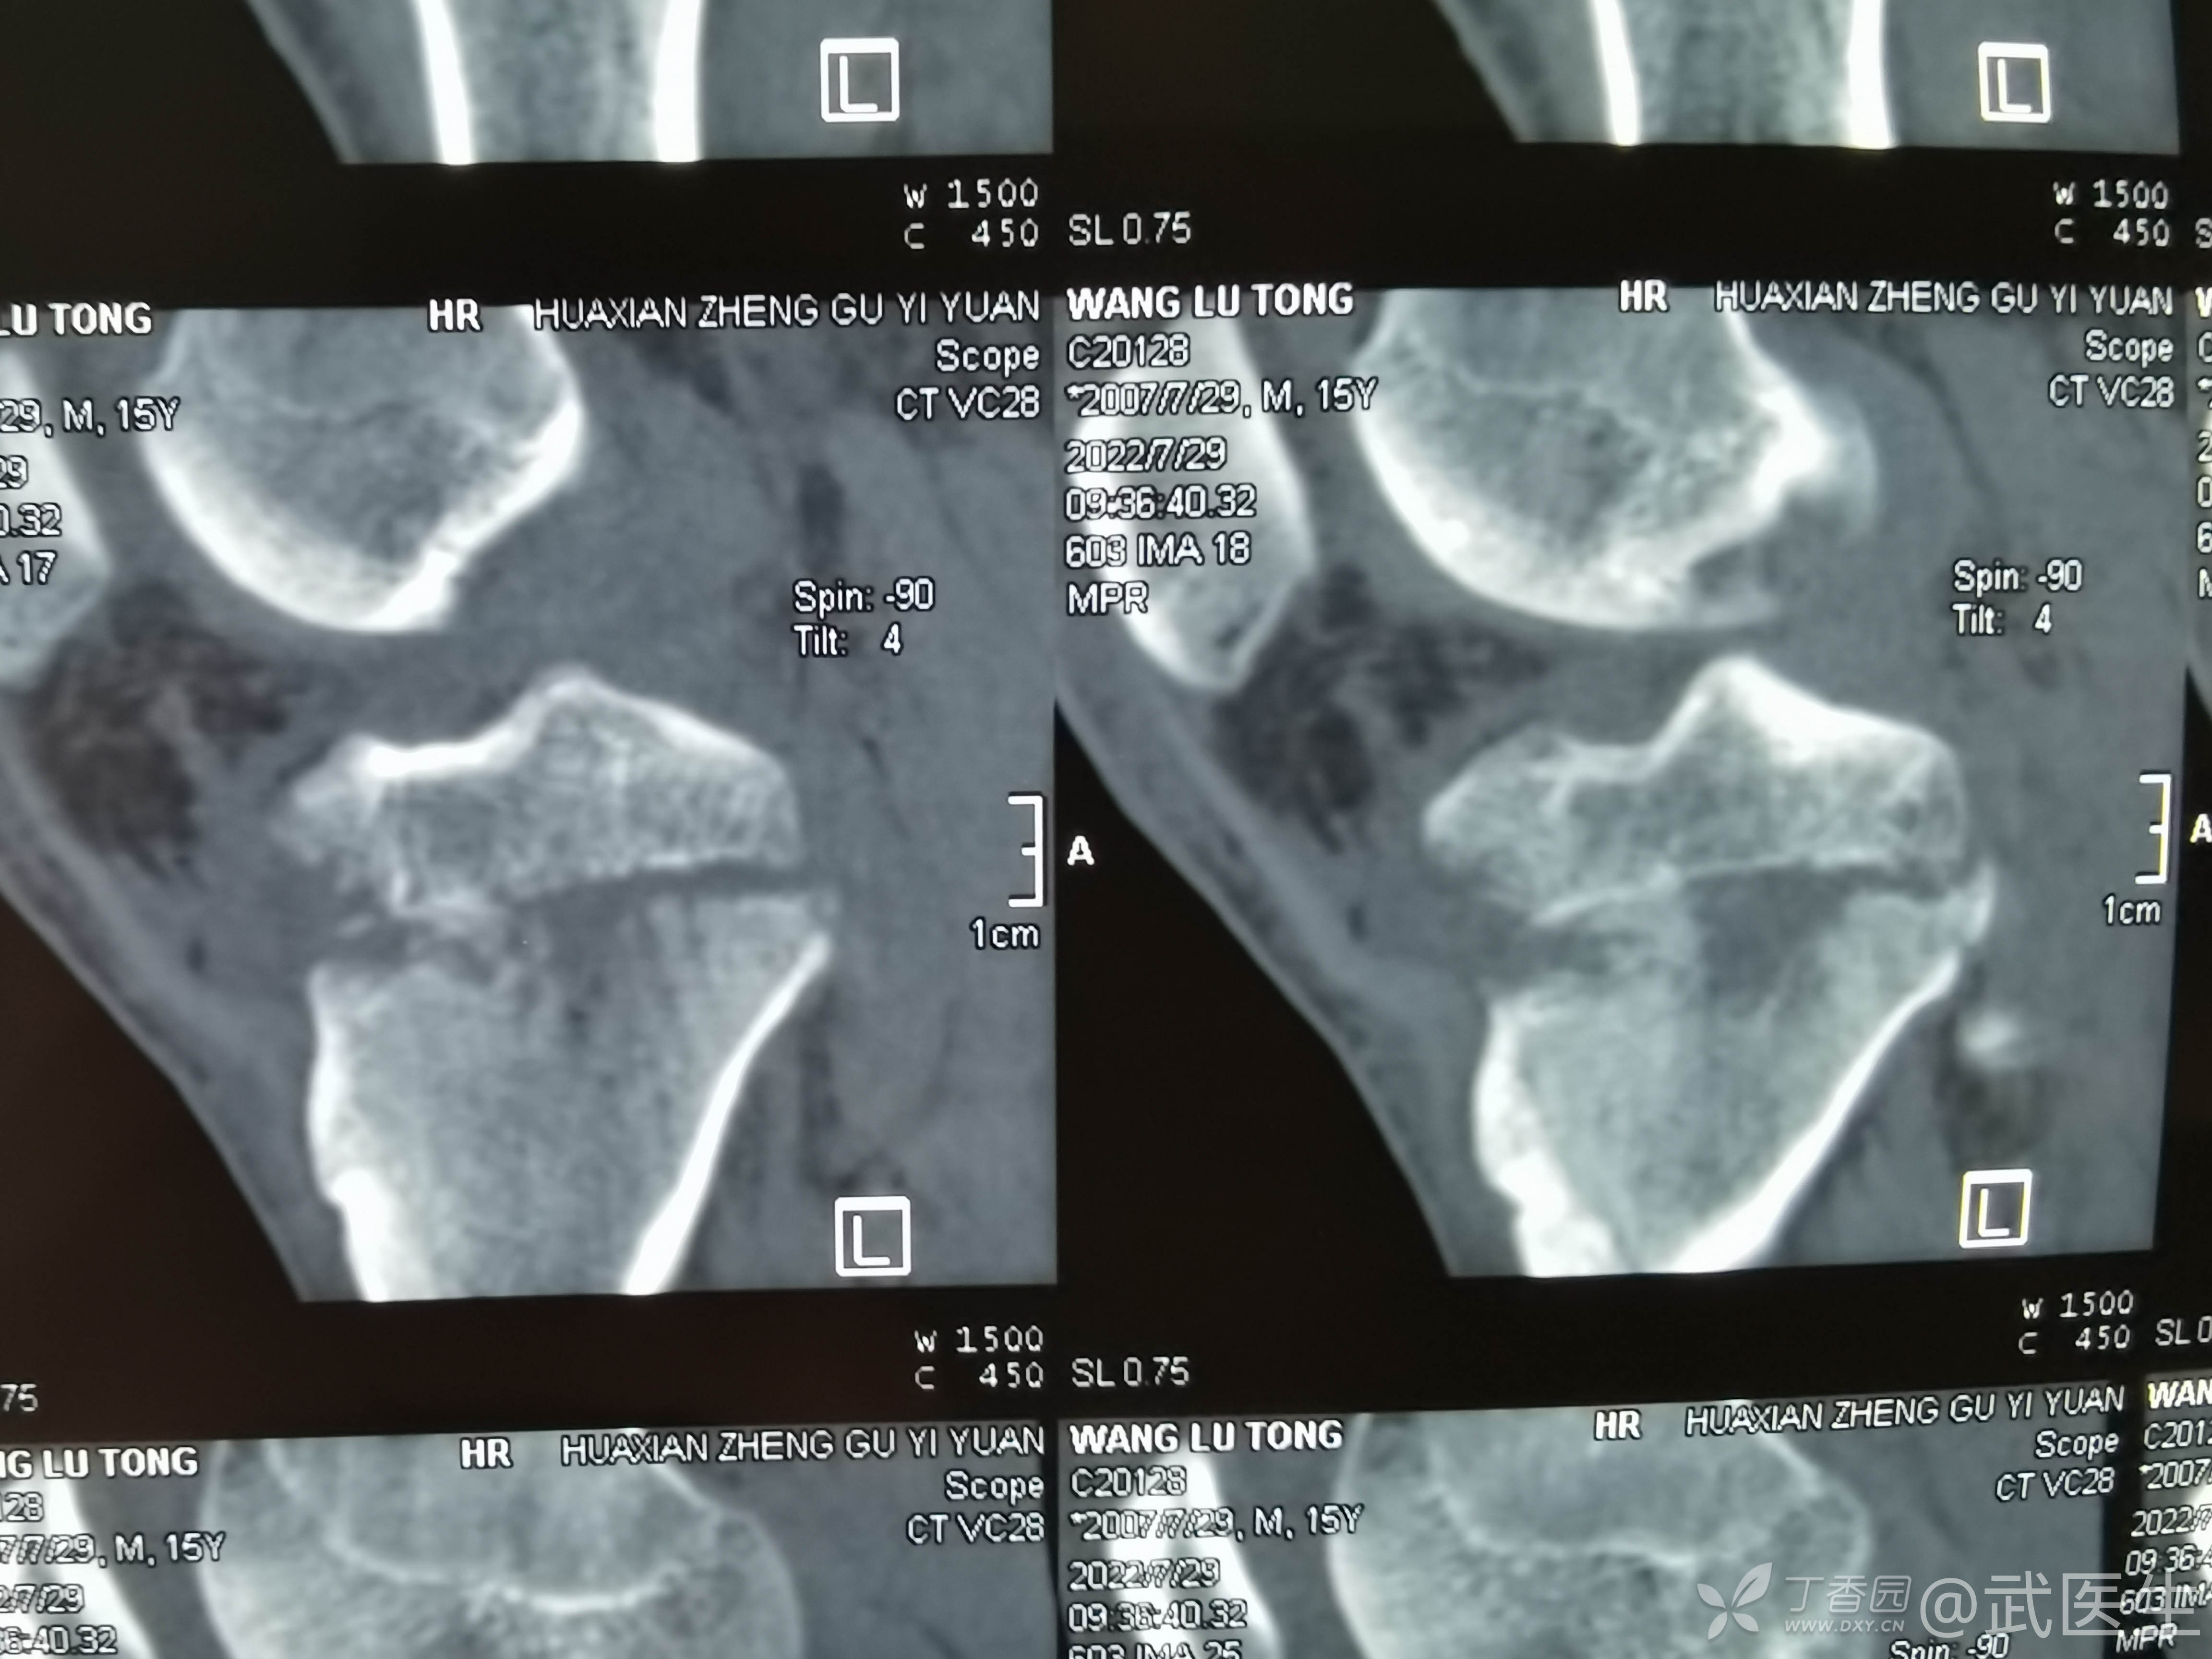

男,15岁,骑摩托车摔伤致右膝疼痛,出血,活动受限三小时就诊,门诊诊断“右胫骨平台骨折,右膝挫裂伤”急诊入院,片子如下,受伤体位照缺失

15岁,骨骺存在,关节加压固定,外侧板支撑